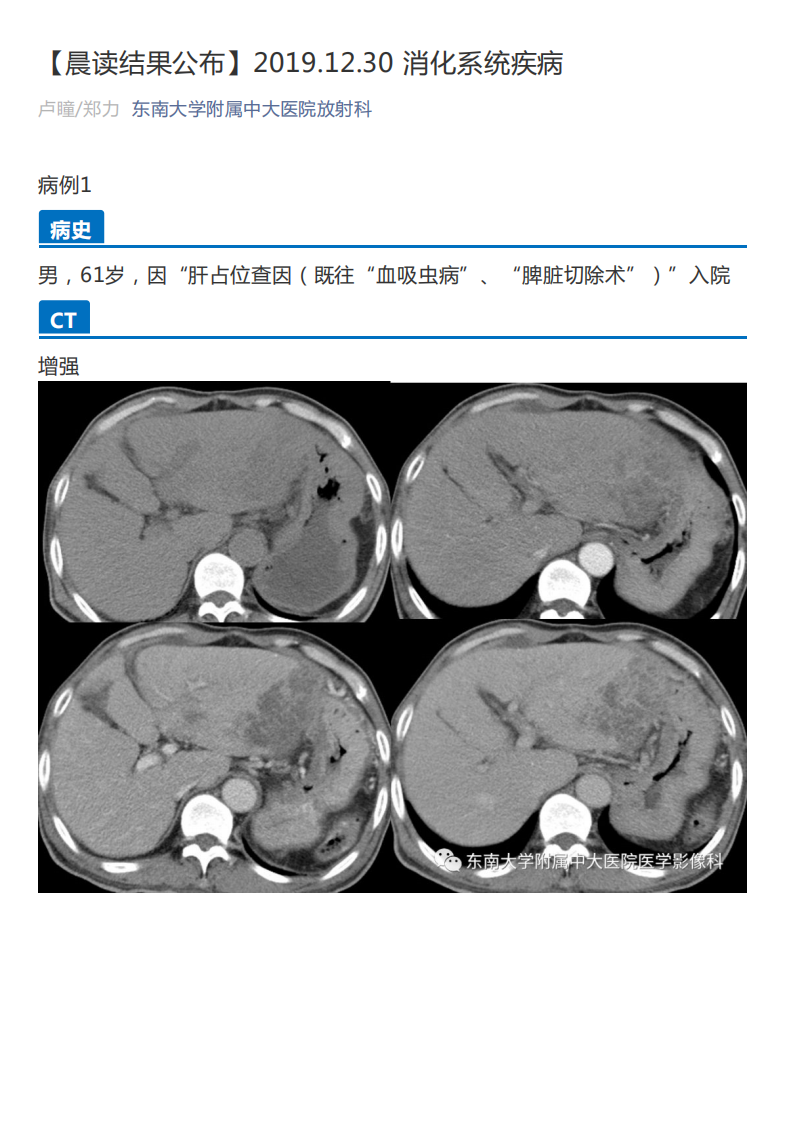

20191230_2【晨读结果公布】2019.12.30消化系统疾病.pdf